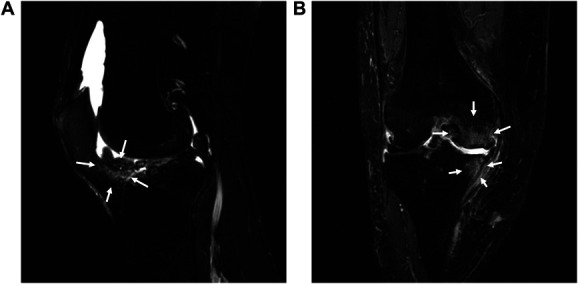

Methods: A total of 86 patients were assessed for demographic characteristics, osteoarthritis severity, Whole-Organ Magnetic Resonance Imaging Score-Hoffa synovitis and bone marrow lesions, pressure pain threshold and temporal summation of pain at the knee and forearm, Central Sensitization Inventory-9, and MEP. In measure of MEP, knee pain was scored using a numerical rating scale (NRS, 0-10) before and every minute during a 6-minute walking test (6MWT), and the MEP index was defined as the change in NRS pain score from baseline to the sixth minute of walking.